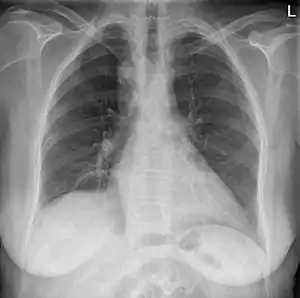

| Anterior-posterior chest radiograph showing a right-sided aortic arch | |

After birth, a right-sided aortic arch is visualized on chest radiography, by the aortic knob (the prominent shadow of the aortic arch) that is located right from the sternum instead of left. Complex lesions are often assessed by MRI or CT.